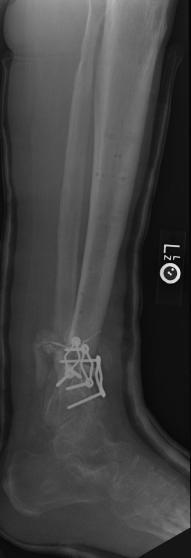

Post-infection X-Rays of the damaged right & left legs / ankles

After the last surgery Liam developed Staphylococcal (staph) infection as well as Osteomyelitis on the bone. Liam went to the ER of

Tempe St. Luke with a temperature of over 104 degrees and severe pain of the left leg. Liam was released from the ER with a diagnosis of

Gastroenteritis and instructions to follow up with a visit to Dr. Armendariz. Four days later and with a continued very high temp, Liam was

seen by Dr. Armendariz. Dr. Armendariz immediately performed 3 surgeries to clean out the infected areas of both the left and right leg and

to place wound vacs on the damaged areas of the legs.

An interesting point to note, as it applies to the second and third x-rays (from the left), is the placement of the last screw at the bottom

of the right legs fibula plate. Notice how Dr. Keller completely missed the plate. Not only is the screw useless, but it has started protruding

in such a way as to cause severe pain and require padding to keep from bursting through the skin. A later surgery is planed for the screws

removal.